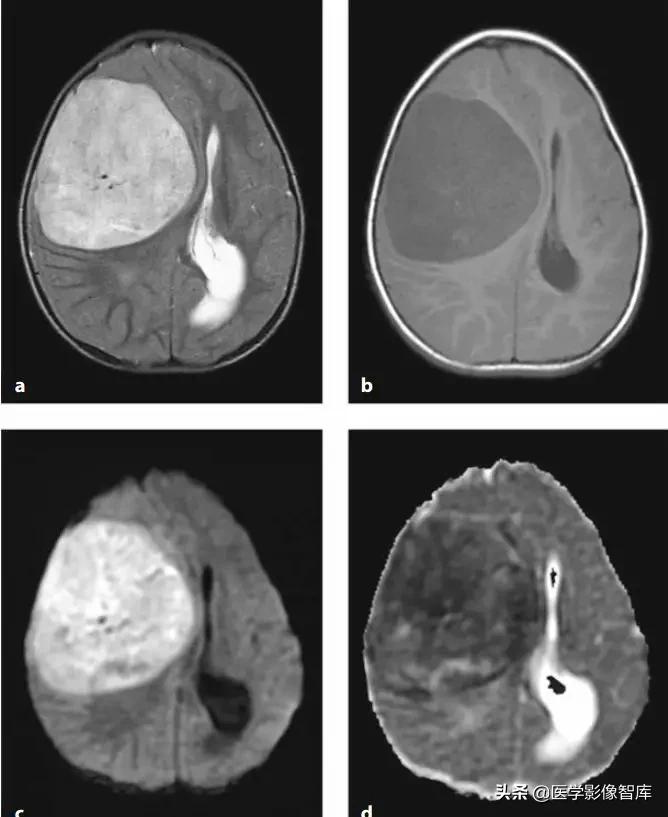

图12 髓母细胞瘤(DWI高、ADC低)